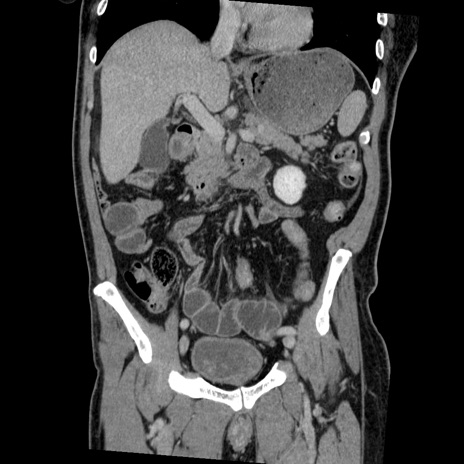

症例22(冠状断像)

【症例】50歳代男性

【主訴】腹痛

【現病歴】AVMからの被殻出血のため回復期リハ病棟入院中。 本日午後3時頃急に下腹部痛が出現した。

【既往歴】AVM、被殻出血、虫垂炎、高血圧

【身体所見】意識晴明、左半身不全麻痺、会話の理解は良好、36.5°C、腹部:膨隆、全体に板状硬、下腹部正中に圧痛点あり、反跳痛-、筋性防御不明、右下腹部にope scar

【データ】WBC 9400、CRP 0.06